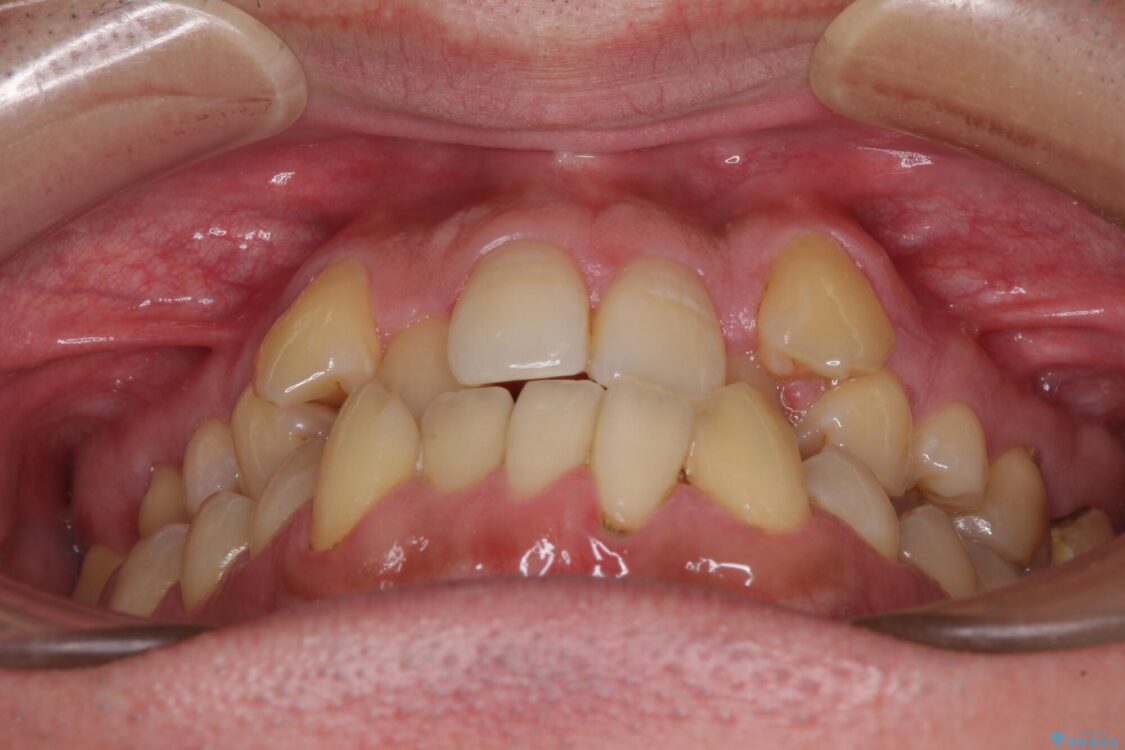

八重歯と前歯のクロスバイトを改善したいとのことで来院された患者様です。

デコボコの程度は強かったのですが、口元の突出感はなかったため、非抜歯矯正としました。

治療前

• 八重歯とクロスバイト 目立たないワイヤー装置で矯正治療 治療前画像